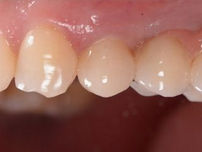

STRAUMANN® iEXCEL | CLINICAL CASE

LOWER MOLAR TOOTH REPLACEMENT IN HEALED SITE

Freehand surgery for a lower molar tooth replacement in a healed site using an apically tapered Straumann® BLC implant ∅ 4.5 mm x 12 mm SLActive®, Roxolid®, and following a conventional loading protocol.

Dr. Algirdas Puišys